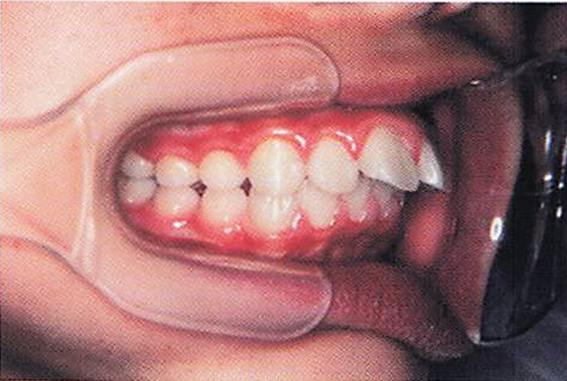

午前-55

10歳の女児。上顎前歯の歯ならびが気になることを主訴として来院した。 顔面写真、口腔内写真および治療に用いた装置の写真を別に示す。 期待できる効果はどれか。1つ選べ。

a.下顎前歯の唇側移動

b.下顎骨の前方成長促進

c.上顎大臼歯の近心移動

d.上顎骨の前方成長抑制

解答を見る

d